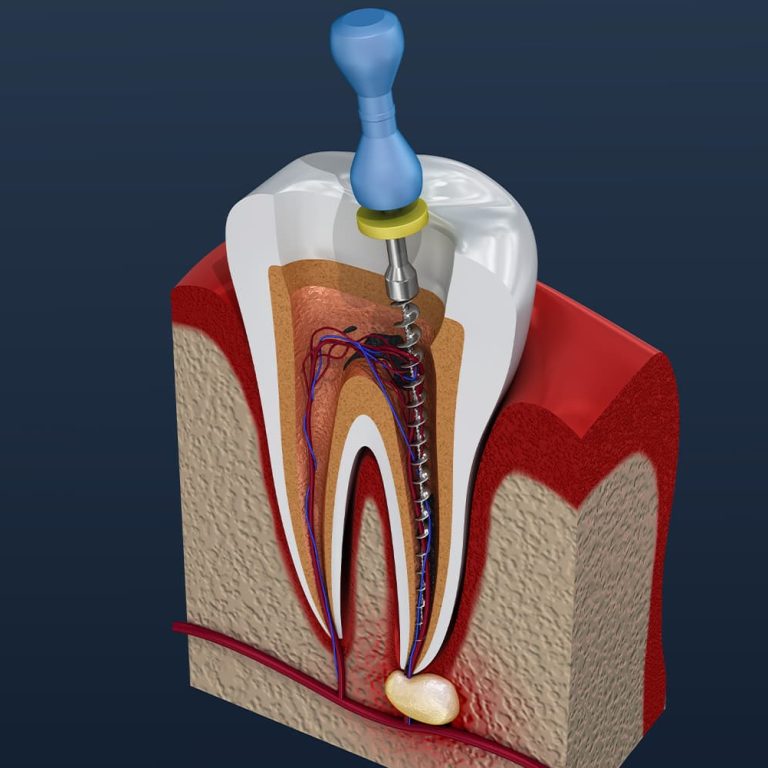

Root canal treatment is an essential procedure to save infected or severely decayed teeth, restoring function and relieving pain. At Satellite Smiles, our expert dental team uses advanced techniques to perform precise, comfortable root canals tailored to your needs. The process involves removing infected pulp, cleaning the tooth’s inner chamber, and sealing it with biocompatible materials to prevent further issues. Using state-of-the-art imaging and gentle methods, we ensure minimal discomfort and effective results. Our personalized care includes post-treatment guidance to promote healing, helping maintain a healthy, confident smile for years to come.

Our precise root canal techniques eliminate infection and discomfort, restoring your tooth’s health for a pain-free, confident smile.

Using cutting-edge imaging and tools, we ensure accurate, efficient treatment, minimizing discomfort and promoting successful outcomes for every patient.

Biocompatible materials seal and protect treated teeth, preventing future issues and preserving your smile’s strength and natural function.